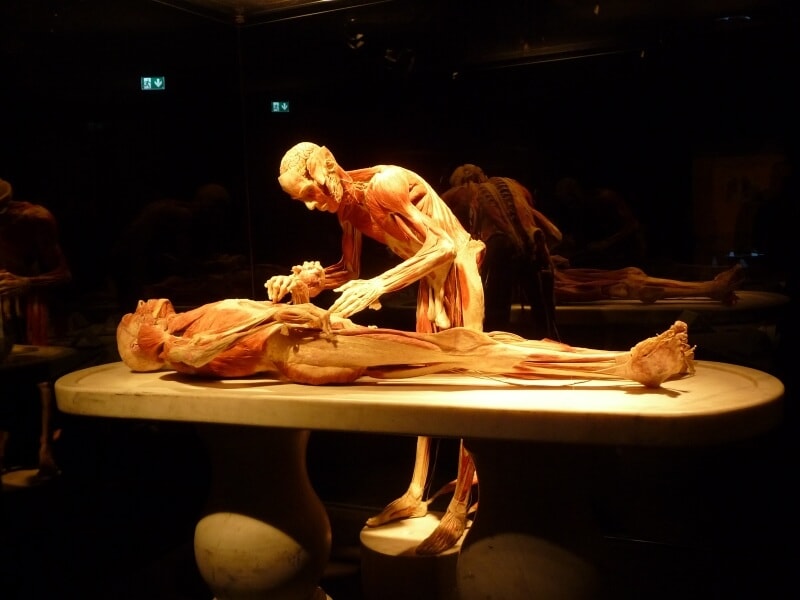

Falck hanyatt fekvő helyzetben székek közé kötözi, Tiegel sűrű dróthálóba varrja, míg Manassin egy hosszú vászoncsíkkal mintegy élve bebalzsamozza, egyben melegíti az állatot.

Harmincz évvel ezelőtt, kísérleti kórtani búvárkodásom kezdetén, gyakran éreztem hiányát egy ideális fölfeszítésnek. Végül, nehéz próbálkozások után, létrejött ezen egészen új készülék, amellyel az állat felkötése a következőképpen történik:

Az alsó és felső keresztléczek a deszka közepére húzatnak, a szorító sodronyok kinyittatnak, majd a kísérleti sapkával nyugalomba hozott állat, természetes ülő helyzetben, a deszkalapra tétetik. A végtagok ekkor többnyire maguktól a deszkán végighúzódó két árokba igazodnak, vagy könnyedén abba igazíthatók. Most az alsó keresztlécz a két talp felé húzatik, és a szorító sodrony a sarokcsont fölött bezáratik, a felső szorító által a mellső végtag is fix állásba helyeztetik. Most következik a medencze fixírozása, a vasív hirtelen föltétele, a kapcsok bezárása, a csavarszorító becsavarása – így.